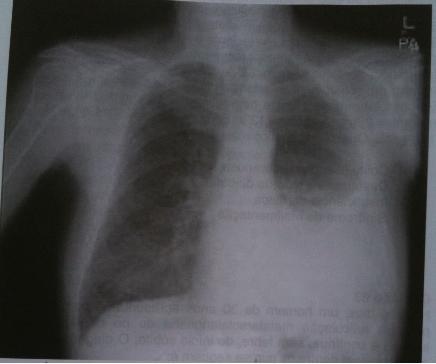

As seguintes alterações podem ser encontradas ao exame físico do paciente cuja radiografia (VER IMAGEM), em correspondência com a área de hipotransparência:

A ) Expansibilidade simétrica e frêmito tóraco-vocal reduzido.

B ) Frêmito tóraco-vocal aumentado, expansibilidade reduzida.

C ) Som maciço à percussão e sons respiratórios aumentados.

D ) Sons respiratórios e frêmito toracovocal abolidos.

—> derrame pleural e pneumotórax: frêmito abolido